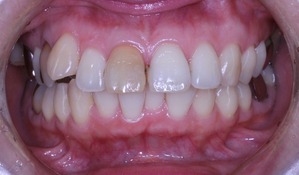

それでは本日の症例です

虫歯治療はきちんとされてますが、奥歯に全部銀歯の状態の歯があります。

当然、神経もない歯です。治療されたのはだいぶ前とのことでした。

患者さんの主訴は口元をひっこめたいでした。

それでは治療経過です

少し経過が進みました

治療開始から3年経過した現在の状況です

もともとは